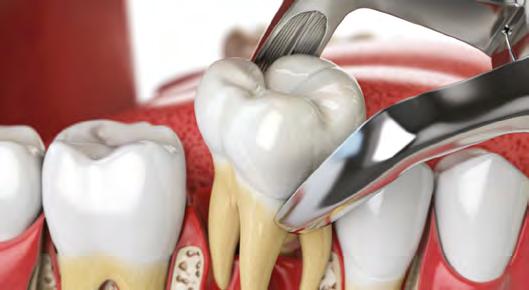

52 | SONRIENDO AL FUTURO

Tratamiento ortodóncico en paciente adulto tratado con extracciones de primeros molares permanentes. Reporte de caso

Tratamiento ortodóncico

en paciente adulto tratado con extracciones de primeros molares permanentes. Reporte de caso